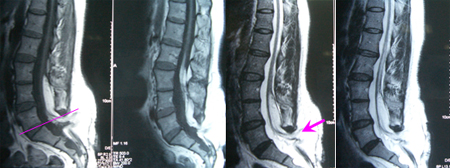

手术在显微镜下进行,术中切除大部分脂肪瘤组织,切断终丝结构,术后影像学资料显示:脂肪瘤大部切除,脊髓圆锥上升约半个椎体节段。术后二便功能改善不明显,下肢肌力恢复,经进一步康复训练后二便功能有所改善。

专家评点:在脂肪瘤型脊髓拴系中,脂肪脊髓脊膜膨出型是最复杂的,术后效果也最差。如果能在诱发电位监测的情况下进行手术,显微镜下游离、切断没有功能的神经结构,保护有功能的神经,终丝切断,脂肪瘤尽可能的减容、切除。脊髓圆锥能充分游离活动、上升的情况下,术后功能的恢复也不是完全没有希望。